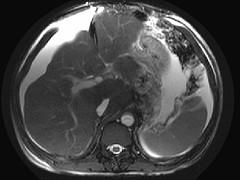

问题 男,44岁,有乙肝病史,现腹胀,右上腹痛,消化不良,消瘦、乏力、贫血、黄疸,血清转氨酶升高,白蛋白/球蛋白比值倒置。CT、MRI检查如下图,最准确的诊断是 ( )

选项 A.肝硬化并腹水 B.肝硬化并腹水、再生结节 C.肝硬化腹水、肝癌 D.肝硬化并再生结节 E.肝硬化并腹水、脂肪肝

答案 B